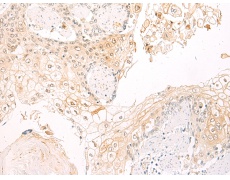

IHC positive control: |

Human esophagus cancer |

IHC Recommend dilution: |

50-100 |